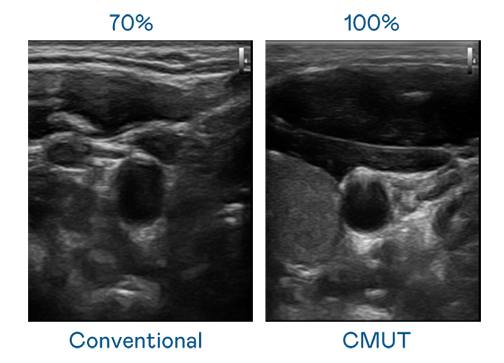

CMUT 技术是一种用电容式微机电元件来产生超音波讯号的技术。与传统 PZT 压电式技术相比,CMUT 频宽增加 30%,更宽频的超音波讯号让影像解析度大幅提升,是实现高影像品质医疗超音波扫描、促进精准医疗发展的关键技术。

大频宽带来超清晰影像

超音波影像的解析度高低,首先取决于探头能发出的讯号频宽。创世大发 CMUT 可提供高清晰的超音波讯号,提供高频宽、高灵敏度、影像纹理细节更高的超音波影像,协助医护人员缩短影像判读时间及利用精准的医疗影像进行诊断。